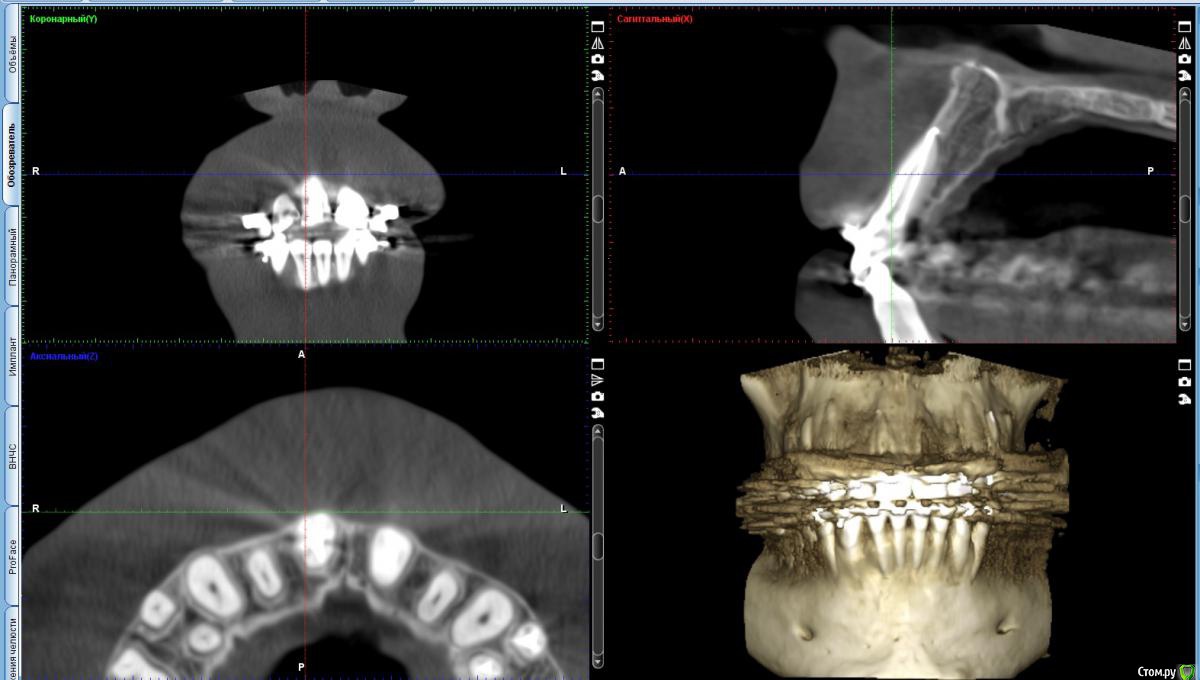

Почти год допекает 11-й зуб. Прошлой осенью пролечили глубокий кариес и сделали реставрацию, затем зуб начал ныть и в феврале этого года его депульпировали. Зуб успокаивался очень долго, месяцев 5, если не больше. Беспокоила именно боль при постукивании/надавливании, сам по себе зуб никогда больше не болел. На вертикальное надавливание реакции нет, а вот при горизонтальное, когда как бы раскачиваешь зуб на или от себя, реакция есть. Достаточно даже просто задеть губой брекет на этом зубе. Флосс между 11 и 12 протискивается с теми же неприятными ощущениями. После очередных активаций у ортодонта зуб первую неделю при прикосновении болит пуще прежнего, а затем опять успокаивается до текущего уровня.

Ни один терапевт при просмотре КТ и снимков ничего не находил, кроме материала за верхушкой. Никакого смысла перелечивать не видят. Чувствительность чаще всего списывают на нагрузку от брекетов, но за последний месяц я дважды оставался без дуги и никаких изменений в чувствительности нет.

В чём может быть причина такой реакции зуба на надавливание? Есть ли смысл делать КТ конкретно этого сегмента (будет ли больше информативность)?

КТ на облаке (445 Мб) - https://cloud.mail.ru/public/woLr/qTpX69i4r Срезы для передних зубов, к сожалению, делать не умею.

Прикрепляю срез. Видно материал на верхушке. Но болезненная перкуссия в таких случаях вроде как при вертикальных нагрузках, а не горизонтальных.